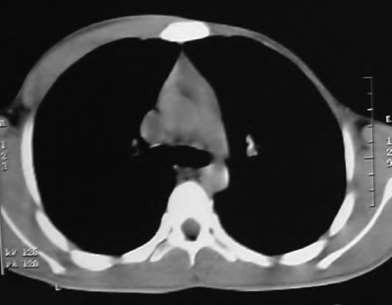

A 35-year-old woman reports wrist pain after a fall onto an outstretched hand. On exam, she has focal tenderness over the wrist snuffbox. A radiograph and CT image are shown in Figures A and B. What is the proper treatment of her injury?